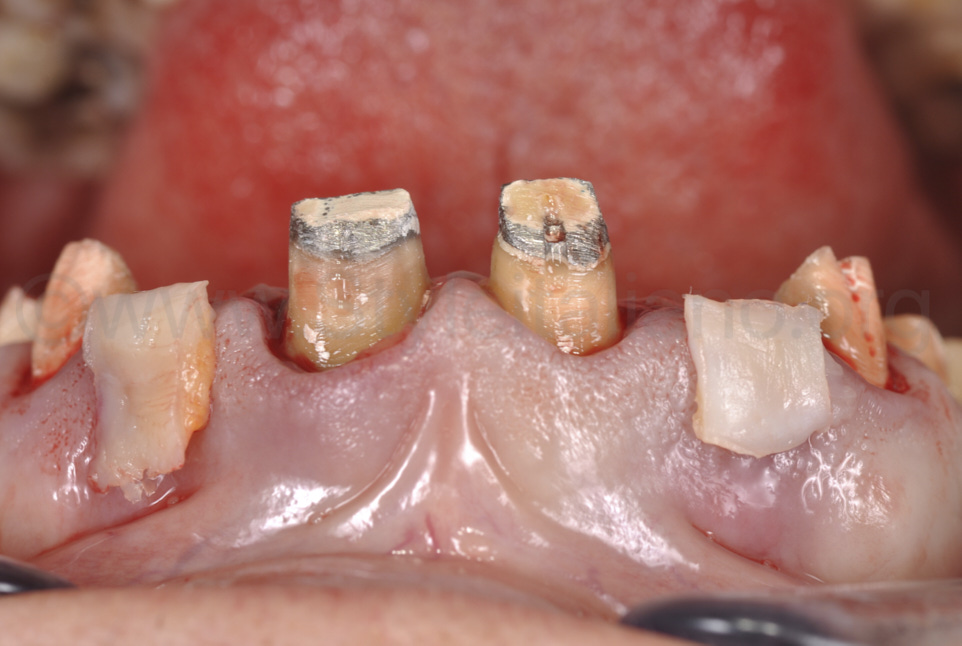

Фото 3.

Якщо розглядати з оклюзійного боку, можна легко помітити, що ясна у зоні двох бічних різців увігнуто. Це слід виправити за допомогою пластичної операції.

Фото 5.

Видалено старі реставрації, та виконано повторне препарування зубів і контурування ясен.